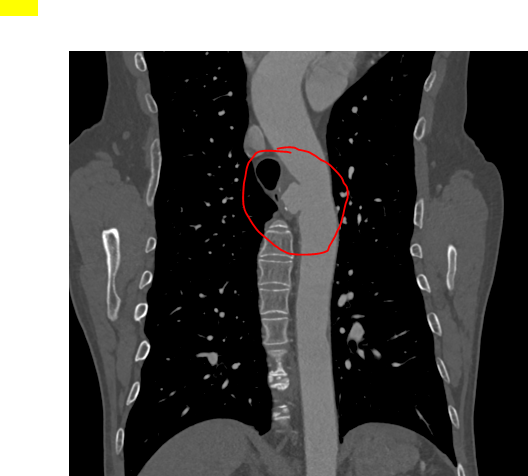

患者乔先生(化名)在查体时意外发现胸主动脉瘤,经主动脉CTA检查确诊后,医生发现其瘤体局部已出现先兆破裂迹象,随时可能发生破裂出血。要知道,胸主动脉是人体最大的动脉血管,堪称生命“主干道”,而胸主动脉瘤就像“体内的不定时炸弹”,一旦破裂,死亡率极高,救治刻不容缓。

一切准备就绪后,手术在全身麻醉下正式开展。手术团队凭借精湛的技术,经患者右侧股动脉穿刺,精准置入导丝及导管,在数字减影血管造影(DSA)的实时引导下,将覆膜支架系统精准输送至主动脉瘤病变部位,确认位置无误后,精准释放支架。整个手术过程精准、高效,仅用半小时便圆满完成。术后即刻造影显示,动脉瘤被完全隔绝,主动脉血流恢复通畅,无内漏、支架移位等异常情况,手术效果达到预期。